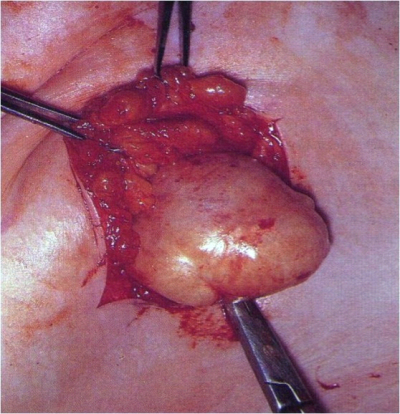

האדנומות מופיעות כגושים עגולים, קשים, אונתיים (לובולריים) וניידים מאוד ברקמת השד. גודלן לרוב אינו עולה על 4-3 ס"מ (תמונה 9.12), אולם קיימות גם פיברואדנומות ענקיות שקוטרן יכול להגיע ל-15 ס"מ ויותר. האדנומות אינן גורמות לתגובה פיברוציסטית סביבן, ואינן גורמות לשינויים בעור או בפטמות. לעתים נדירות, כאשר המסה גדלה במהירות, היא עלולה לגרום לנמק של העור מעליה. בספרות מדווחים על מקרים נדירים ביותר של הופעת שאת ממארת בתוך פיברואדנומה.

לצעירות בעלות שאתות ענקיות של השד יש להוציא את האדנומה דרך חתך בקו התת-שדי (Inframammary) לקלף את השד מדופן בית החזה, לפתוח את הקפסולה של הפיברואדנומה הזו ולהוציא אותה בשלמותה. יש לסיים את הניתוח בתפירת העור בתפר תוך-עורי (תמונה 12.12).